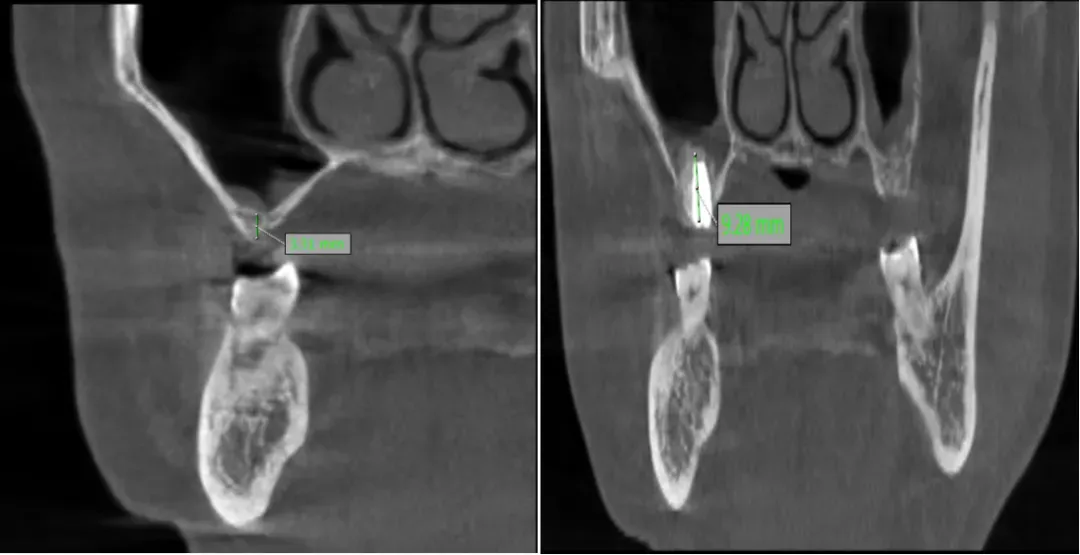

種植牙成功的核心在于充足的骨量支撐,對(duì)于骨量嚴(yán)重不足的患者,術(shù)前精準(zhǔn)評(píng)估與科學(xué)規(guī)劃非常重要。延安市中醫(yī)醫(yī)院口腔科閆慧鑫主任帶領(lǐng)團(tuán)隊(duì),結(jié)合患者全身健康狀況、口腔功能需求及美學(xué)期待,運(yùn)用三維CBCT影像技術(shù)對(duì)頜骨進(jìn)行全方位、立體化掃描分析。通過(guò)精準(zhǔn)測(cè)量剩余牙槽骨的高度、寬度,明確上頜竇位置與形態(tài),同時(shí)模擬手術(shù)全過(guò)程與修復(fù)效果,最終為患者制定了上頜竇外提升同期種植體植入的個(gè)性化手術(shù)方案,讓每一份骨量都能得到充分利用。

術(shù)前骨高度? ? ? ? ? ??術(shù)后骨高度及種植體